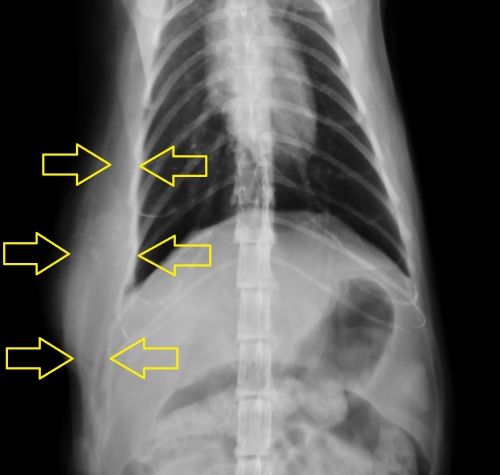

下写真は注射部位肉腫の可能性のある腫瘤の外観写真です。左写真が上から、右側が側面像です。

大きな腫瘤が広範囲でなだらかに正常組織と連続しているために写真では判断しにくいですが、赤線内の硬い腫瘤の周囲は裾野をかたちづくるように正常組織と固着しており境界は不明瞭ではっきりしていません。

この腫瘤は病理検査の結果、未分化肉腫であるという診断が出ています。